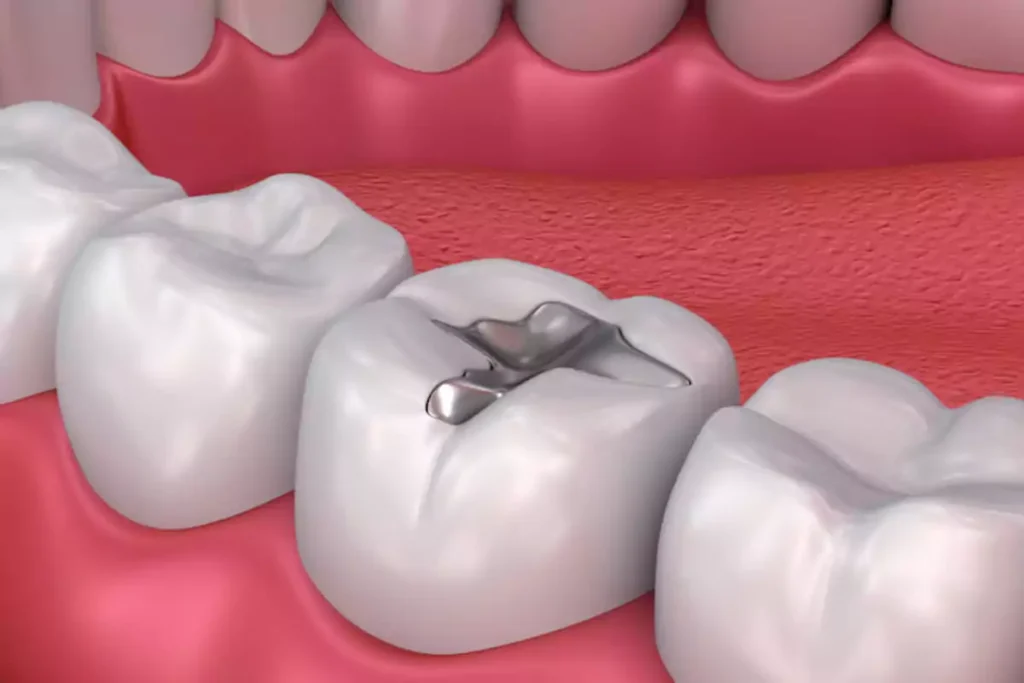

6. حشوات الأملغم

تُستخدم حشوة الأملغم لملء الفجوات بعد معالجة تسوس الأسنان أو الكسر، وتتميز بمكوناتها المعدنية مثل الزئبق والفضة والقصدير والرصاص.

مكونات ومميزات حشوة الأملغم

- تتكون من خليط من المعادن (الزئبق، الفضة، القصدير، والرصاص)

- تتميز بمتانتها العالية وتدوم لفترة طويلة

- تُستخدم بشكل رئيسي في الأسنان الخلفية بفضل تحملها لضغط المضغ

- تكلفتها أقل مقارنة ببعض أنواع الحشوات الأخرى

عيوب حشوة الأملغم

- لونها الفضي غير جمالي للأسنان الأمامية

- قد تسبب حساسية لدى بعض المرضى من المعادن المستخدمة

- تتطلب إزالة كمية أكبر من نسيج السن

- يمكن أن تُصبغ الأنسجة المتبقية باللون الرمادي